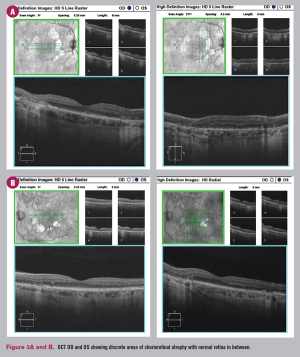

Case exhibits challenge of “atypical” disease presentation and potential for unneeded surgery.